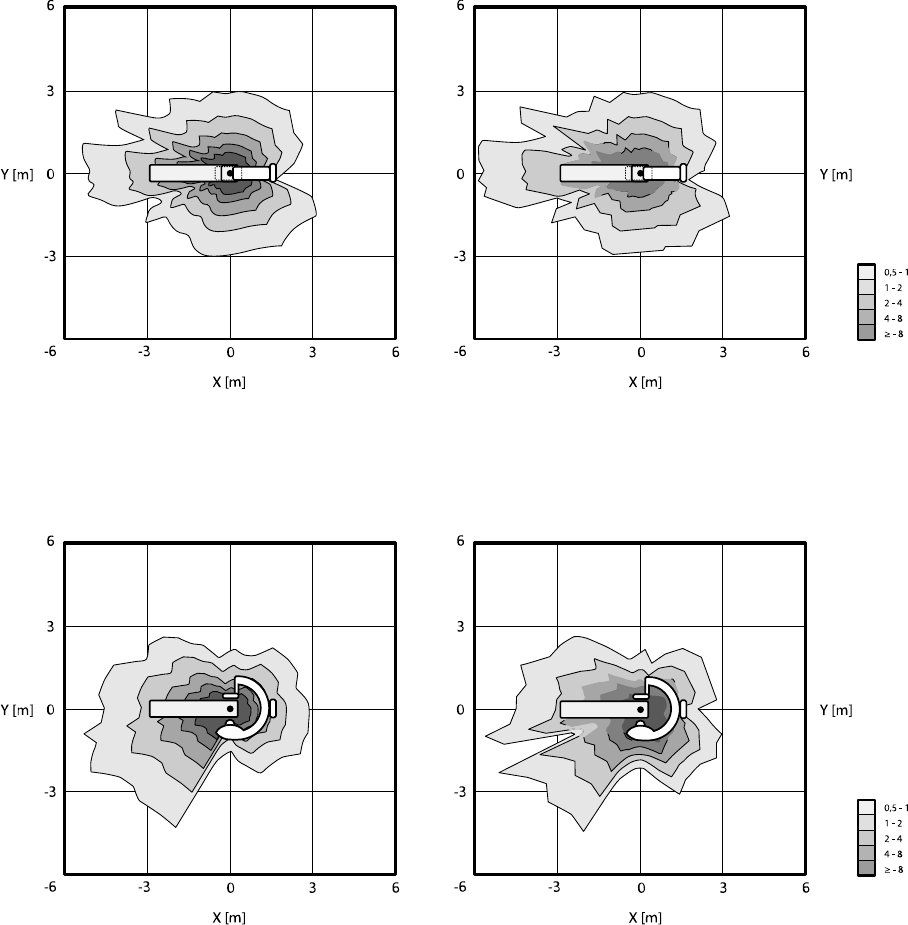

16.21 Ochrona przed promieniowaniem rozproszonym................................................................ 308

16.21.1 Strefa przebywania.............................................................................................. 308

16.21.2 Mapy izokermy systemu C12/F12........................................................................ 310

16.21.3 Mapy izokermy systemu F15................................................................................ 311

16.21.4 Mapy izokermy systemu C20/F20........................................................................ 312